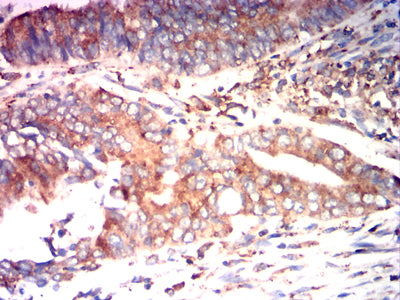

- Immunohistochemical analysis of paraffin-embedded human ovarian cancer tissues using P4HB mouse mAb with DAB staining.

- Immunohistochemical analysis of paraffin-embedded human rectal cancer tissues using P4HB mouse mAb with DAB staining.